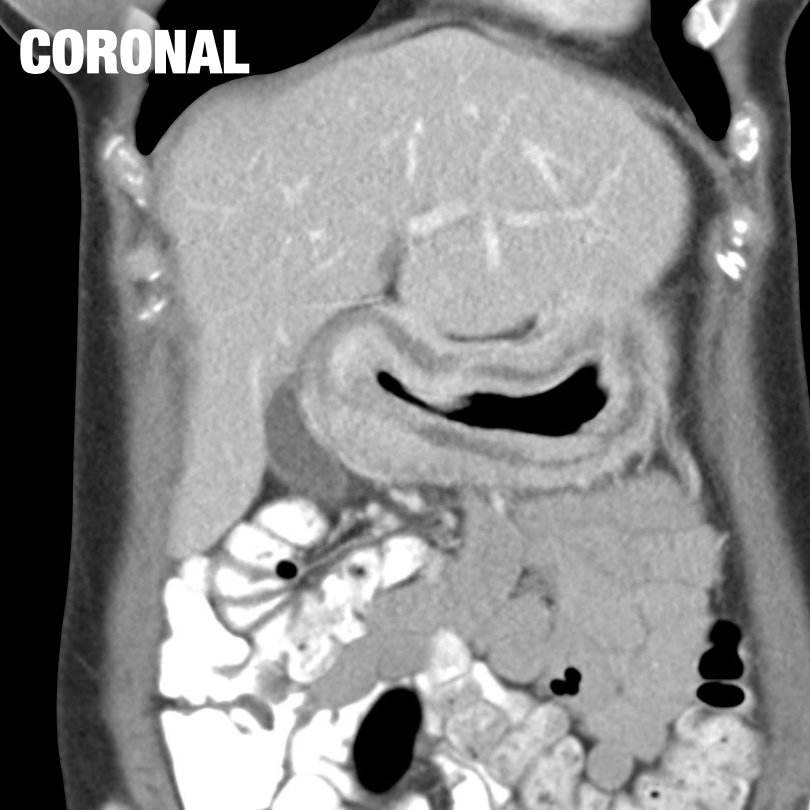

I wish I had a KUB but scout will do! 44-year-old female patient presenting with decreased bowel movements and abdominal distention... what is the name of this sign? GIFs only please! @BrighamRad @FOAMrad @SAR_RFS @futureradres @ARRS_Radiology @Abdominal_Rad @CBRadiologia

Great job! Coffee bean sign in sigmoid volvulus! What are the other signs associated with this condition? Anyone? Anyone?